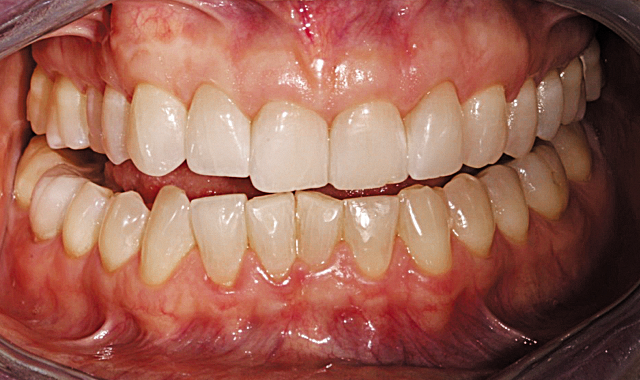

This patient presented with concerns over the esthetics of her smile due to the shifting of her teeth over time (Figs. 1-3). We diagnosed crowding and asymmetry of her teeth and gingival tissues. Our treatment plan included Invisalign treatment, occlusal equilibration after orthodontics and Vivera retainers.

Fig. 2

Fig. 3